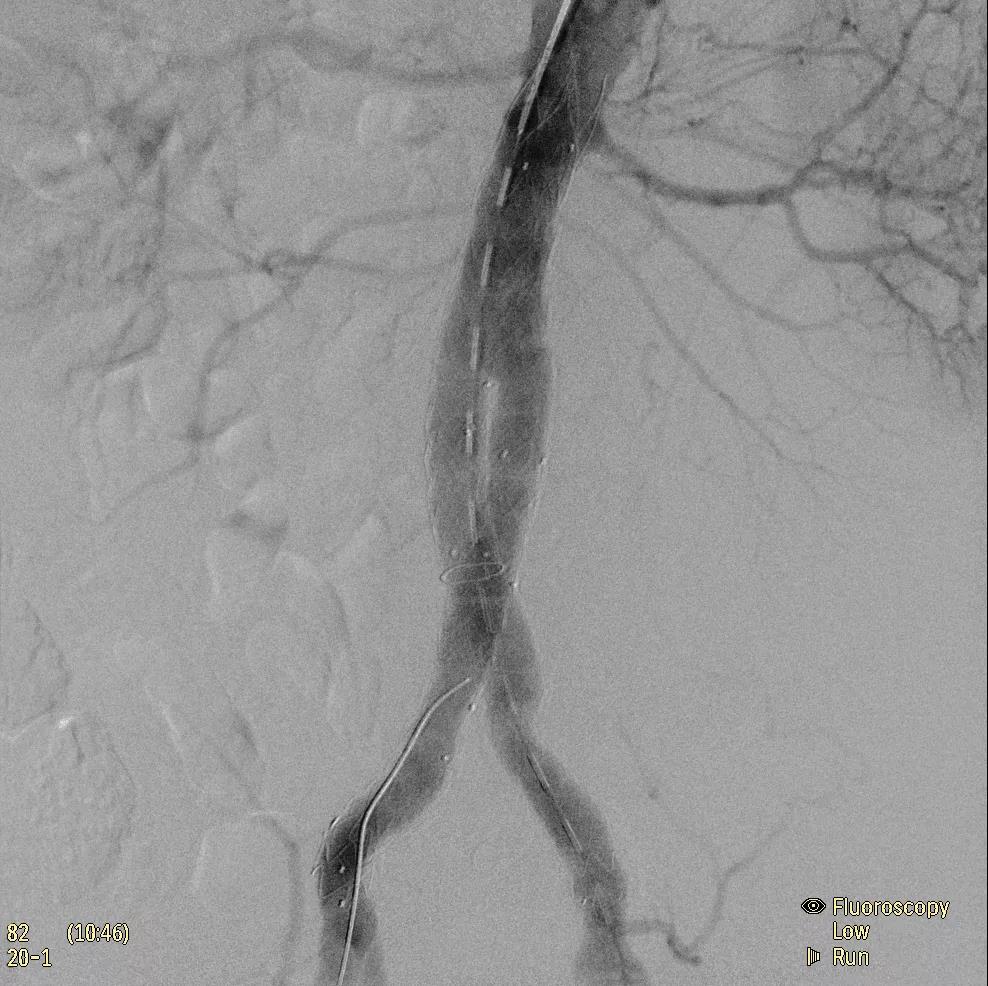

飛利浦于2019年2月18日宣布推出帶扁平探測器的移動式C臂Zenition 70。Zenition 70使用飛利浦第四代Flat Detector系統(tǒng),具有卓越的成像清晰度和靈活性,可執(zhí)行各種情況。

據(jù)器械之家了解到,移動式C型臂是X射線系統(tǒng),可帶入手術室(OR),在整形外科、創(chuàng)傷和血管手術等各種手術過程中提供實時圖像引導。Zenition70使醫(yī)院能夠最大限度地提高OR性能,增強臨床能力并為員工提供高質(zhì)量的用戶體驗。

( Zenition 70匯集了圖像捕獲,圖像處理,易用性和多功能性方面的創(chuàng)新。)

在快速增長的圖像引導微創(chuàng)手術領域 ,手術干預的范圍和復雜性在繼續(xù)增加,需要治療的患者數(shù)量也在增加。為了以更低的成本治療更多的患者,醫(yī)院需要具有不同能力的多功能C臂組,以便容易地適應不同類型的手術和不同操作者的需要。Zenition 70易于在手術室之間移動,易于在患者周圍定位并且操作直觀。

飛利浦Zenition 70支持整個醫(yī)療保健機構提高OR性能。平臺類似平板電腦的用戶界面和簡單的統(tǒng)一工作流程意味著一旦操作員學會在平臺上使用一個系統(tǒng),他們就可以輕松地操作它們。該系統(tǒng)可在任何介入或外科手術過程中快速直觀地拍攝傻瓜相機。Zenition的緊湊設計,位置記憶功能(僅適用于Zenition 70)和BodySmart軟件,即使在圖像增強器或平板探測器的邊緣也能捕捉快速一致的圖像,將C臂重新定位的需求減少45%。

( Zenition 70采用與Azurion平臺相同的圖像處理算法。

為了獲得清晰的高質(zhì)量圖像,Zenition 70 采用了與公司Azurion平臺相同的圖像處理算法,可提供患者解剖結構的高清可視化和更大的可視區(qū)域。飛利浦的MetalSmart軟件等功能可確保圖像質(zhì)量,該軟件可自動調(diào)整圖像的對比度和亮度,以便在視野中存在金屬物體(如植入物)時提高圖像質(zhì)量 - 這一特性使Zenition 70在整形外科中特別有用。